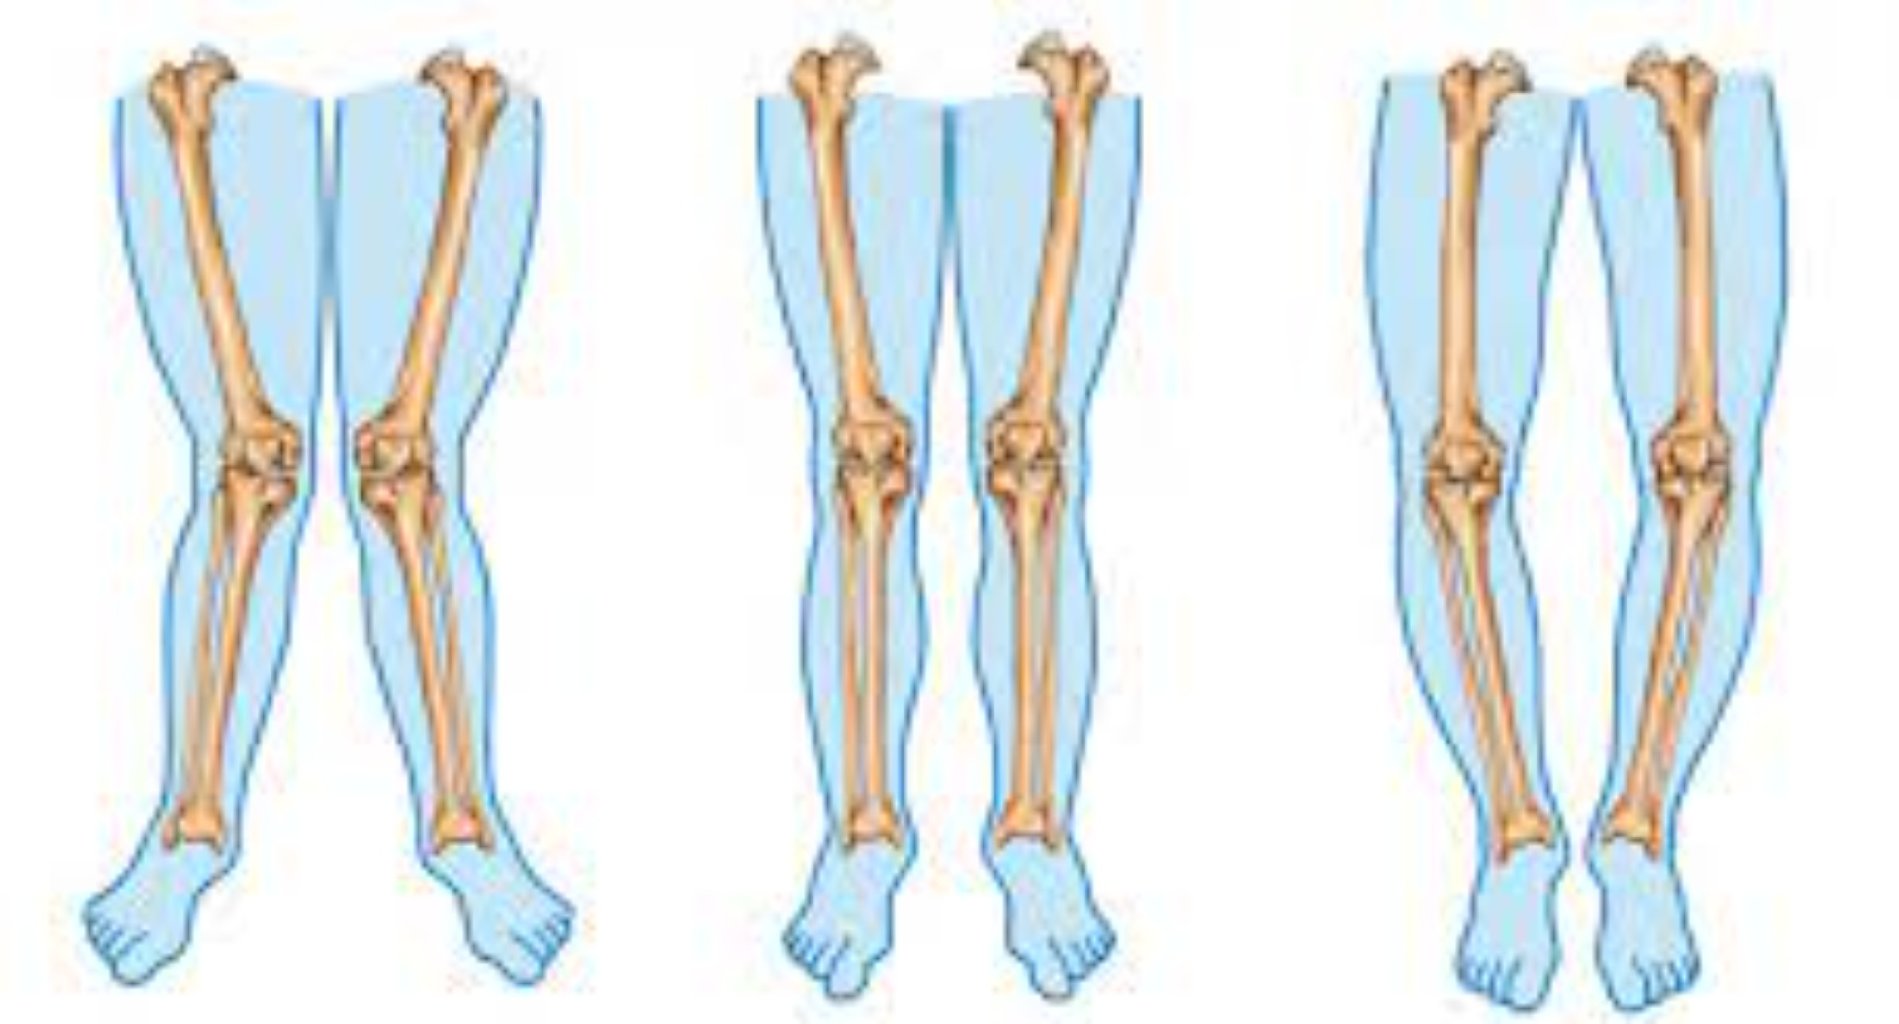

Diz Osteotomiyası: Diz əyilməsi kimi problemlərin düzəldilməsi üçün istifadə olunur. Məsələn, diz os ...